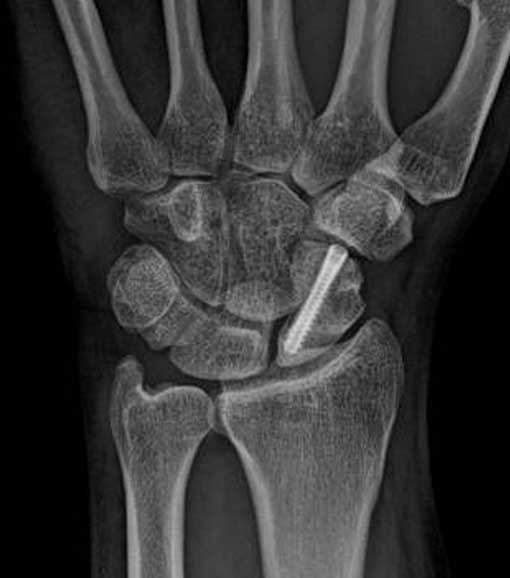

Cerrahi Müdahale: Kırık yer değiştirmişse ya da uzun süre fark edilmemişse, ameliyat gerekebilir. Genellikle vida veya çiviyle kemik sabitlenir.